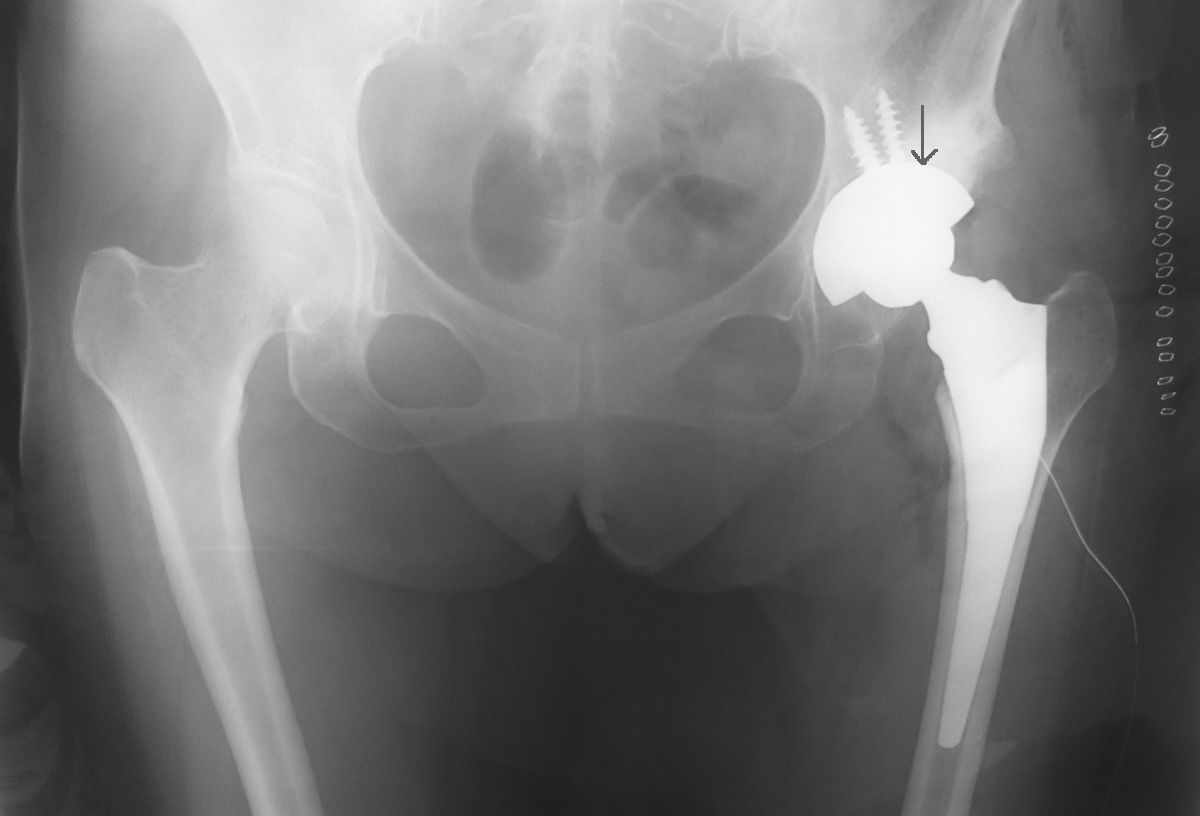

単純X線像のごとく、中~高等度の臼蓋形成不全がある股関節だったので、リーミングを慎重に施行する必要がありました。CTで計測したところ、予定サイズは46>44mmでした。

今朝の症例では上図の矢印の位置がリーミングの上縁です。寛骨臼とカップの間には骨移植を行っています。カップ設置位置の上縁のマーキングは臼蓋形成不全股では勧めの方法です。